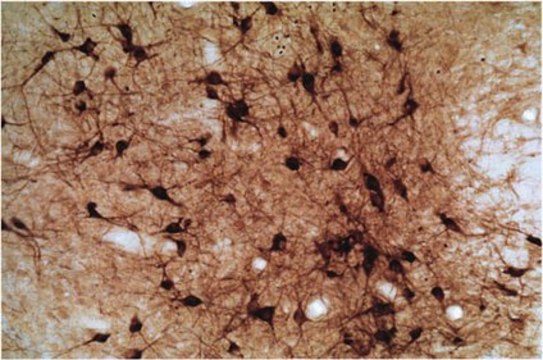

IHC, WB

immunohistochemistry: suitable, western blot: suitable

A 21 amino acid peptide (1409-1429) of the neuronal form of NOS from rat cerebellum, coupled to KLH. The sequence is H-RSESIAFIEESKKDADEVFSS-NH2.

Detect Nitric Oxide Synthase I using this Anti-Nitric Oxide Synthase I Antibody validated for use in WB, IH.

Immunohistochemistry: 1:500-1,000